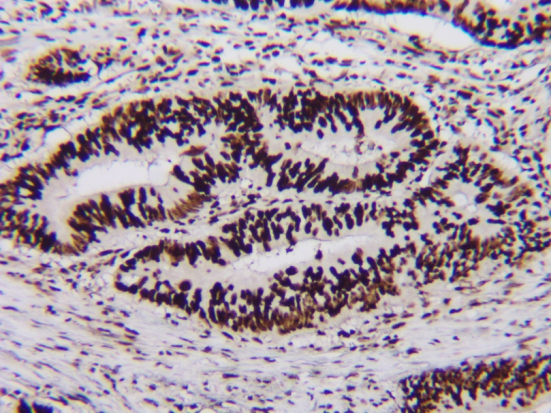

ESLighting®二抗显色系统搭配ESMab®系列一抗

可对靶标抗原进行高清晰,高强度染色。不同灵敏度的显色系统,确保即便是膜/核表达以及其他低丰度抗原也能达到出色的染色效果。